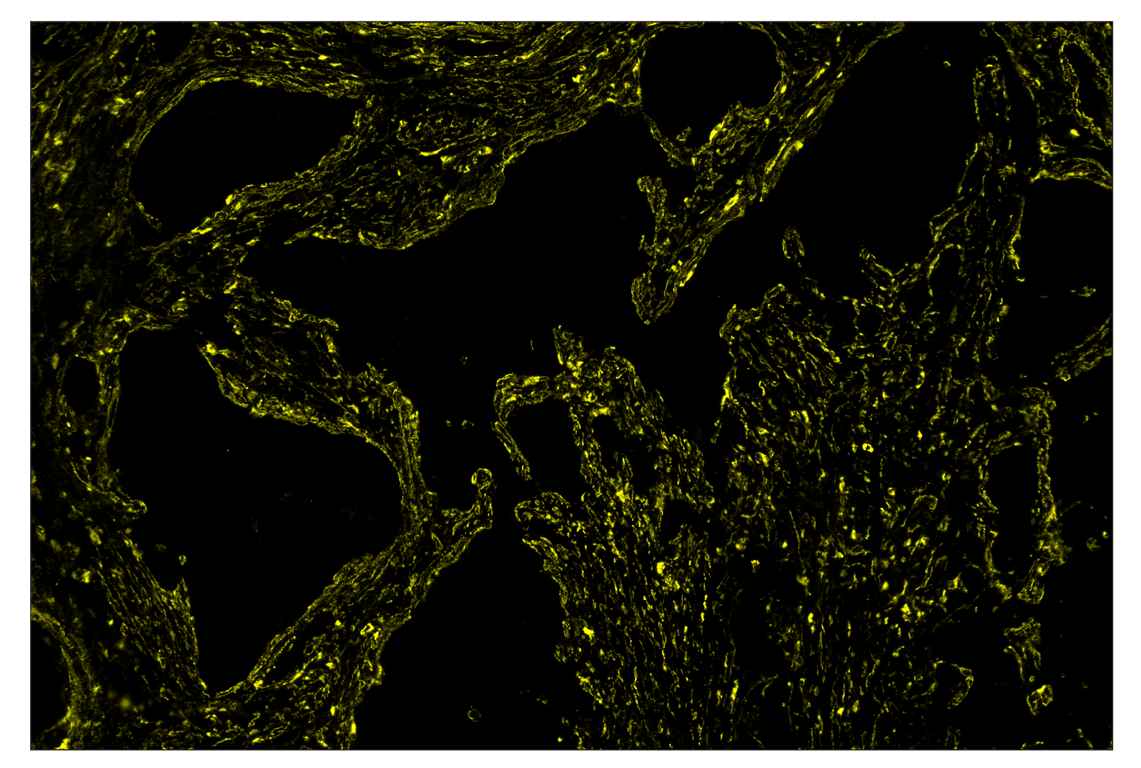

SignalStar™ immunohistochemical analysis of paraffin-embedded human infiltrating ductal carcinoma of the breast using α-Smooth Muscle Actin (D4K9N) & CO-0024-594 SignalStar™ Oligo-Antibody Pair #25040 (yellow). All fluorophores have been assigned a pseudocolor, as indicated. Staining was performed on the BOND RX autostainer by Leica Biosystems.

Immunohistochemistry Image 4: alpha-Smooth Muscle Actin (D4K9N) & CO-0024-488 SignalStar<sup>™</sup> Oligo-Antibody Pair